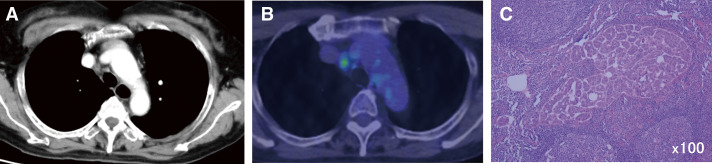

Case presentation: Case 1 was a 50-year-old woman diagnosed with ovarian cancer with mediastinal lymph node metastasis. After 4 courses of chemotherapy, a total hysterectomy, omentectomy, and mediastinal lymph node dissection were performed simultaneously. The patient is still alive 58 months after surgery. Case 2 was a 68-year-old woman who underwent a total hysterectomy after chemotherapy for endometrial cancer with multiple lymph node metastases. Forty-two months after surgery, mediastinal lymph node dissection was performed for metastasis of uterine cancer. She is still alive 75 months after surgery. Case 3 was a 69-year-old woman who underwent a hysterectomy for endometrial cancer. One year after surgery, she underwent thoracoscopic hilar and mediastinal lymph node dissection due to metastasis. Thirty-nine months have passed with no recurrence. Aggressive local control, particularly surgical resection of isolated hilar mediastinal lymph nodes in gynecological cancer, may contribute to prolonging patient survival.